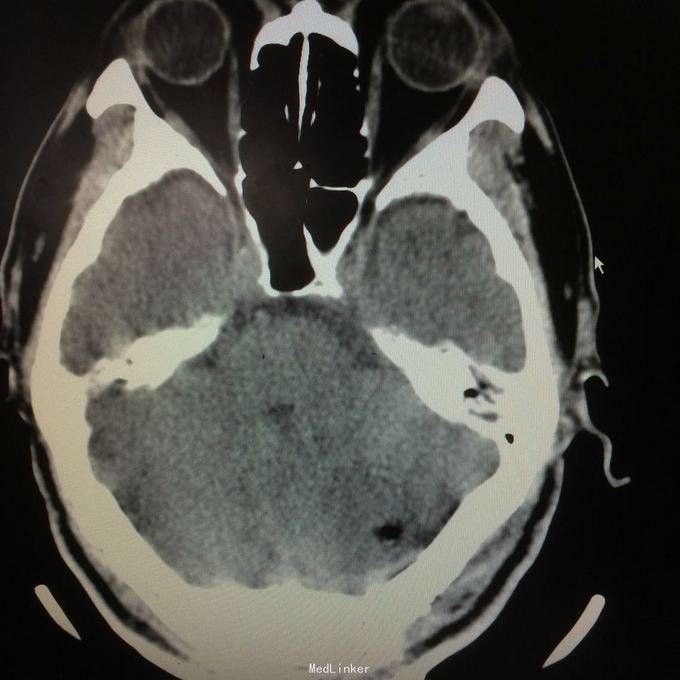

主诉:头晕头痛2年 病史:2年前无明显诱因出现头痛,呈刺痛,程度较重,伴头晕、天旋地转感,1年前查头颅MR提示:左侧小脑半数囊性病变,考虑血管母细胞瘤

查体:神志清楚,病理证阴性 辅助检查:头颅MR提示左侧小脑半数后部囊状占位灶,考虑良性病变。

诊断:左侧小脑血管母细胞瘤 处理:行左侧小脑占位病变切除术,术后病理提示:符合血管母细胞瘤。